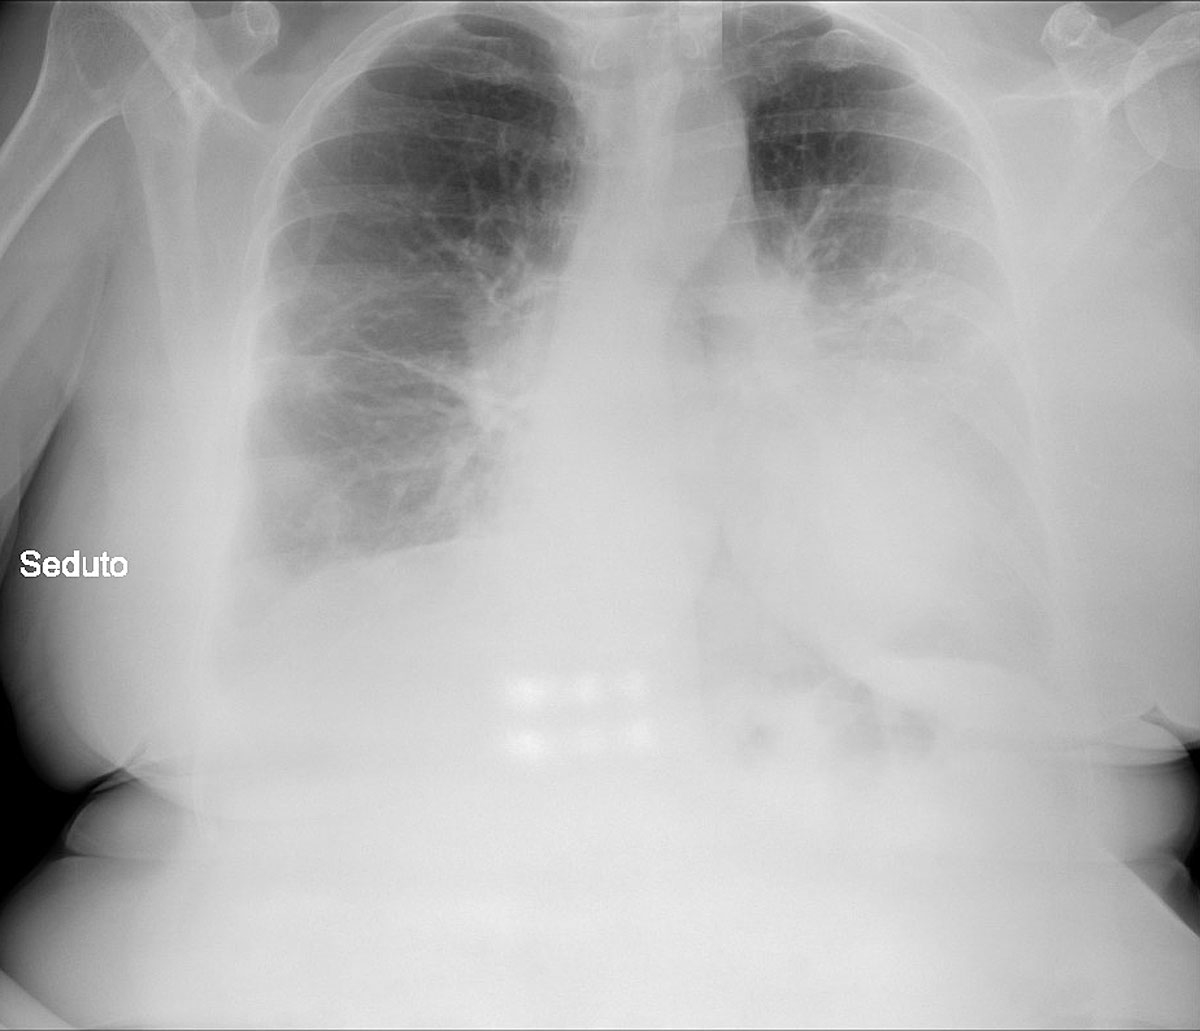

An anteroposterior chest x-ray with the patient in bed and in the supine position, showed “asymmetric” and bilateral diffuse “patchy” parenchymal opacities [22], more marked in the left hemithorax where they were present from the apex to the base (fig. 1). The opacities were predominantly supleural and with a mantellar distribution. They were accompanied by a veil of moderate bilateral pleural effusions, once again more prominent in the left hemithorax.

Figure 1 Chest x-ray of patient 1 on admission, 10 March 2020. Courtesy Ospedale di Sassuolo. In addition to the morphological abnormalities due to the past medical history of the patient and the more recent alterations described in the CT scans performed on 20 February 2020, this image shows opacities strongly suspicious of SARS Cov-2 pneumonia (see description by the radiologist in the text).